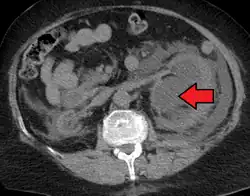

Hydronephrosis due to a kidney stone at the ureteral vesicular junction seen on CT scan

The choice of imaging depends on the clinical presentation (history, symptoms and examination findings). In the case of renal colic (one sided loin pain usually accompanied by a trace of blood in the urine) the initial investigation is usually a spiral or helical CT scan. This has the advantage of showing whether there is any obstruction of flow of urine causing hydronephrosis as well as demonstrating the function of the other kidney. Many stones are not visible on plain X-ray or IVU but 99% of stones are visible on CT and therefore CT is becoming a common choice of initial investigation. CT is not used however, when there is a reason to avoid radiation exposure, e.g. in pregnancy.